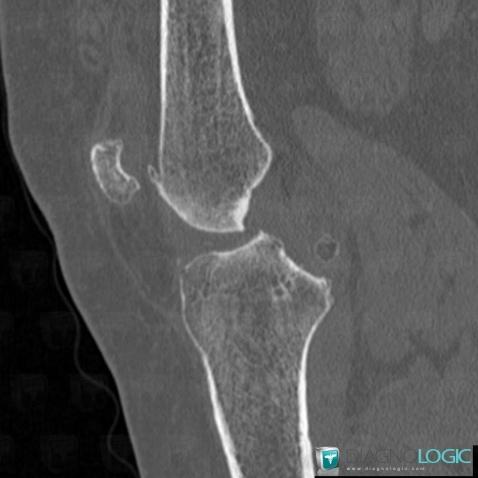

Arthrose, Articulation fémoro patellaire, Scanner

Voici les informations spécifiques à l'image clé ci dessus:

- Diagnostic Arthrose, Localisation(s) Articulation fémoro patellaire, comportant les gammes